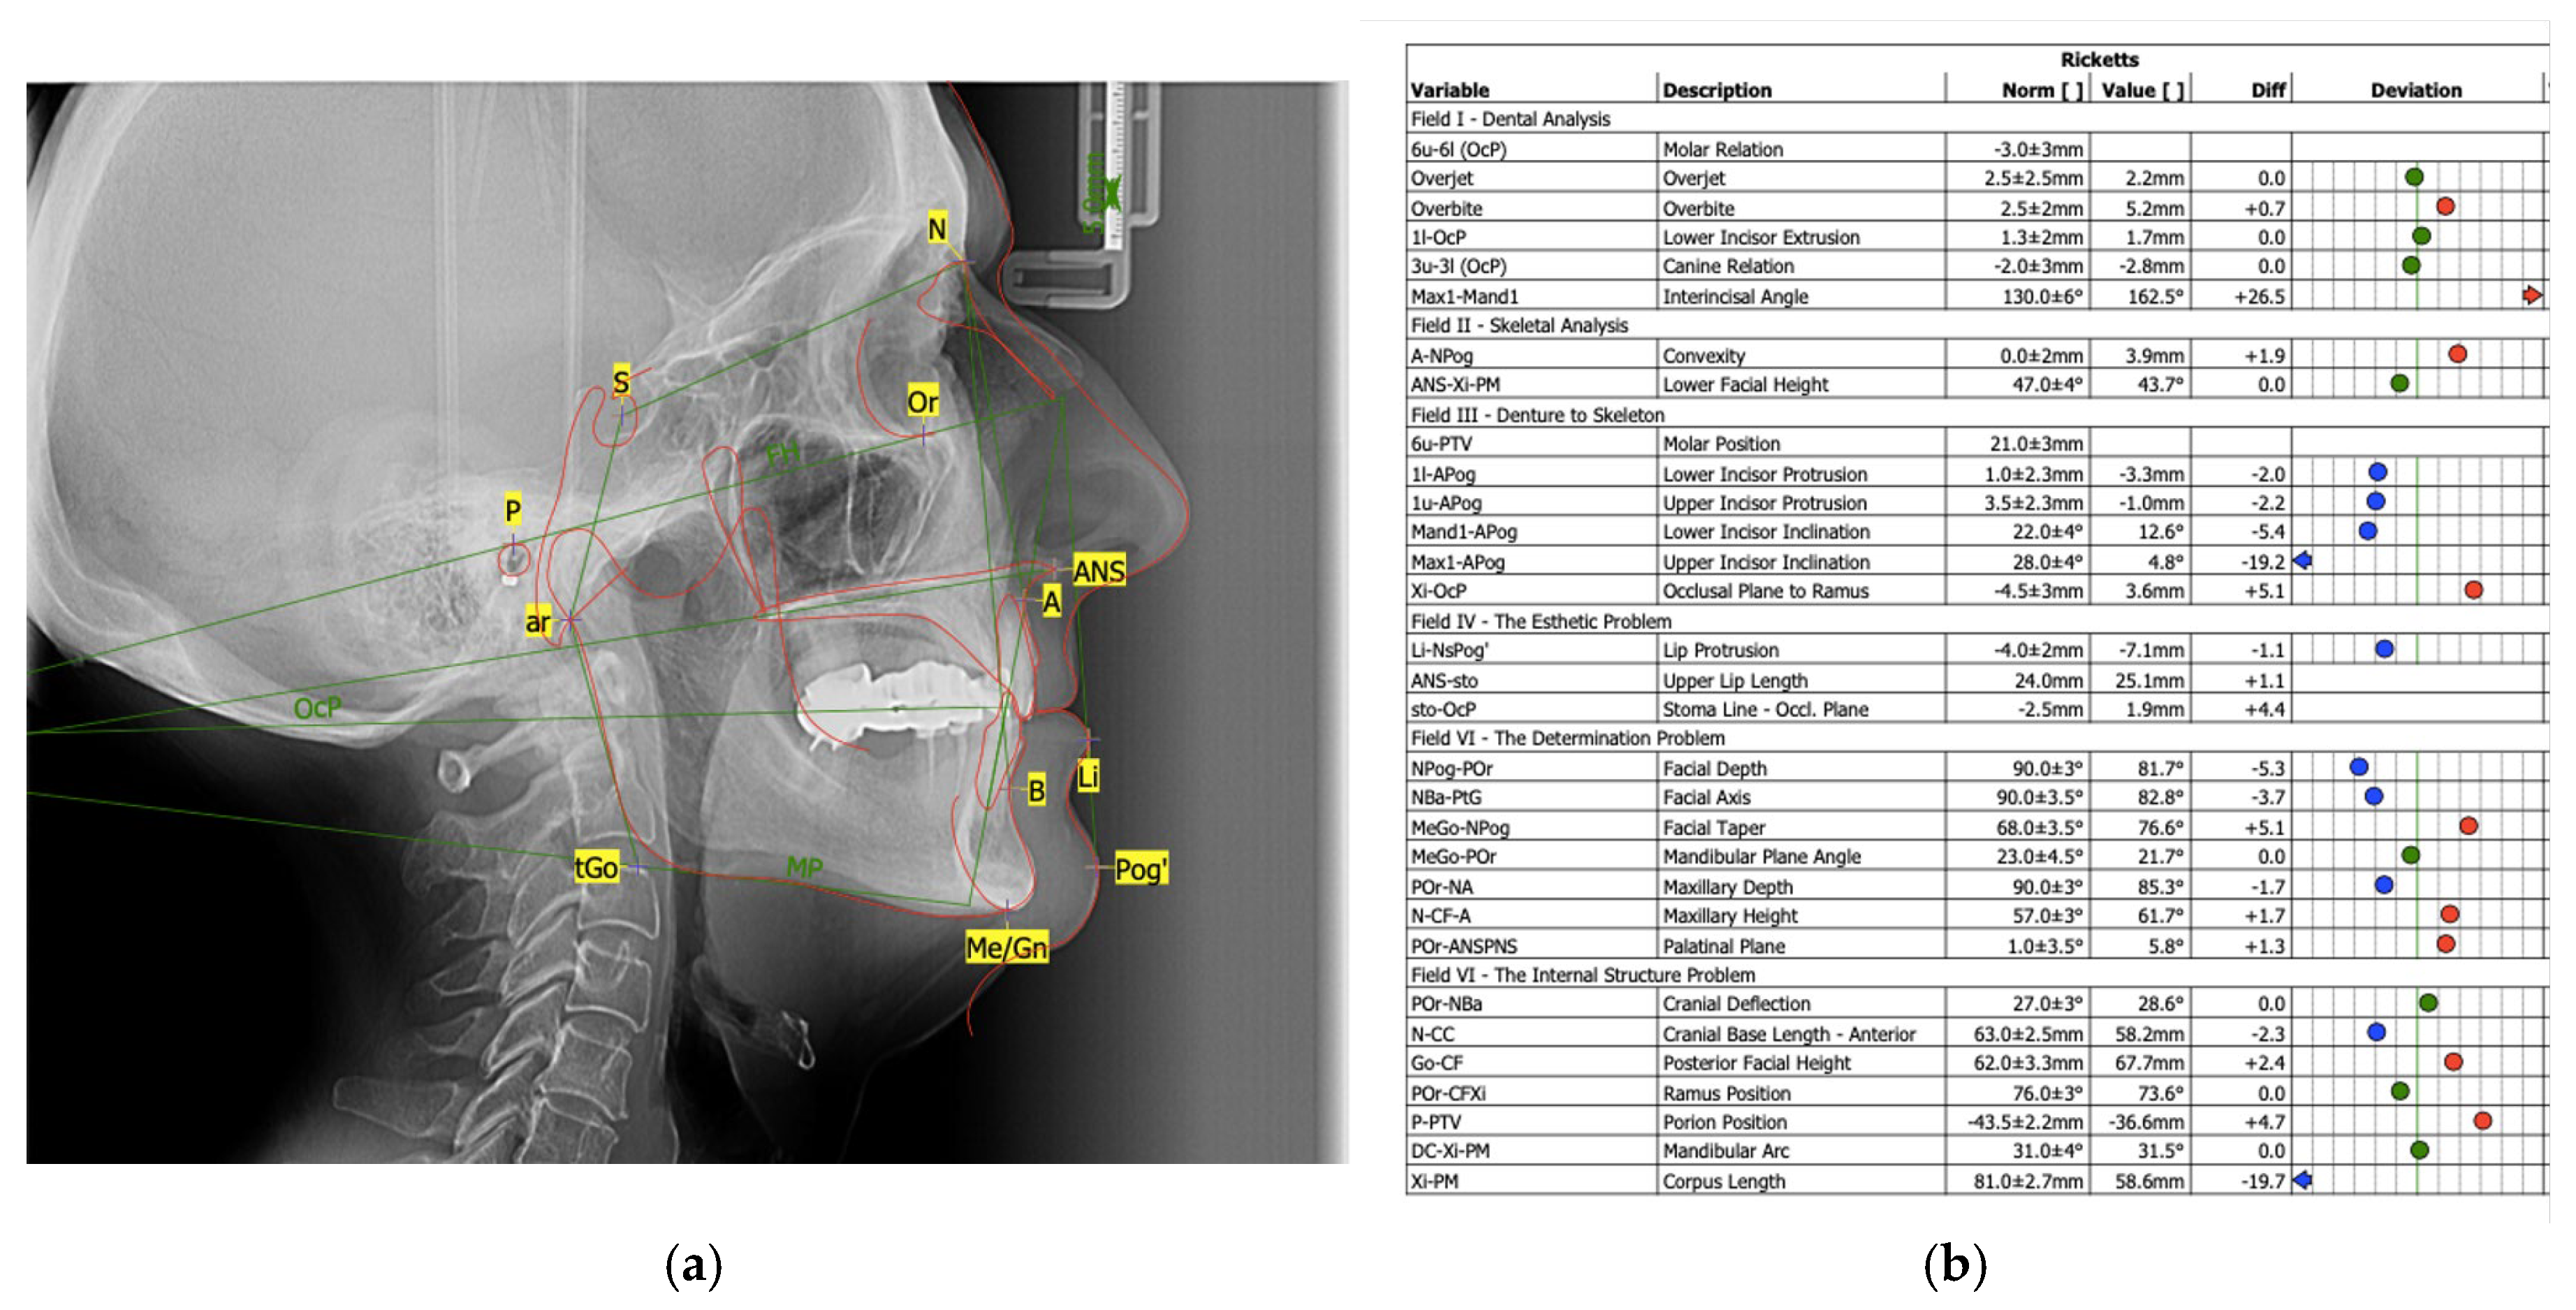

4.1. Case 1

4.2. Case 2